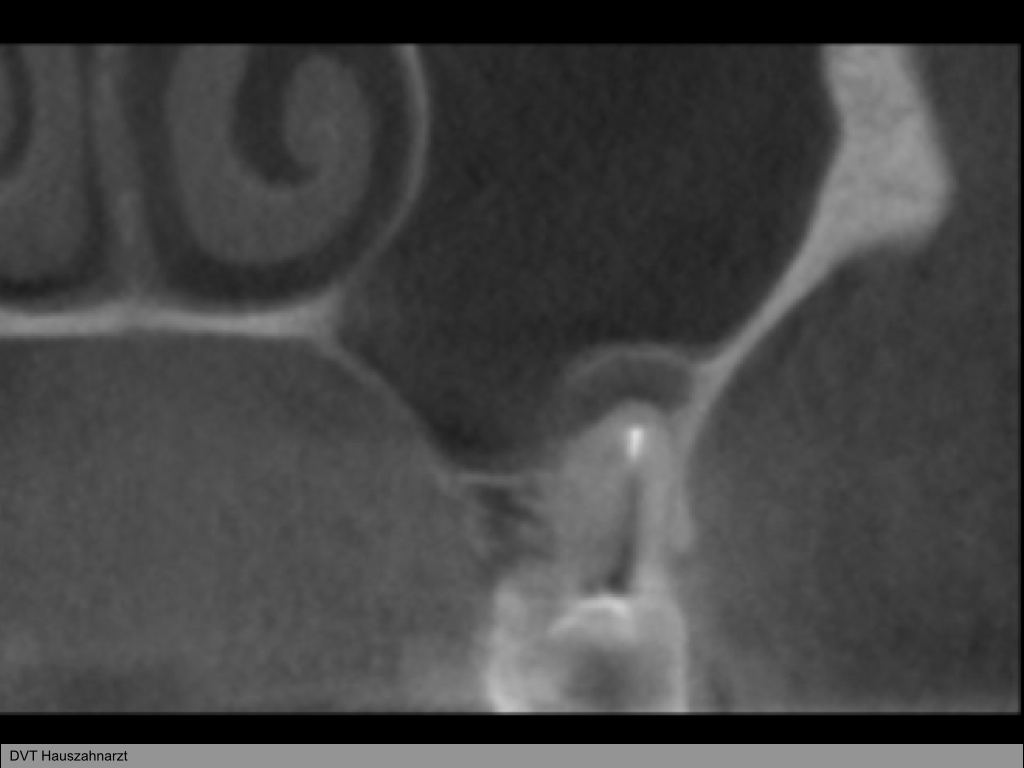

WS8.004

1024 × 768

Instrumentenfraktur (3a)